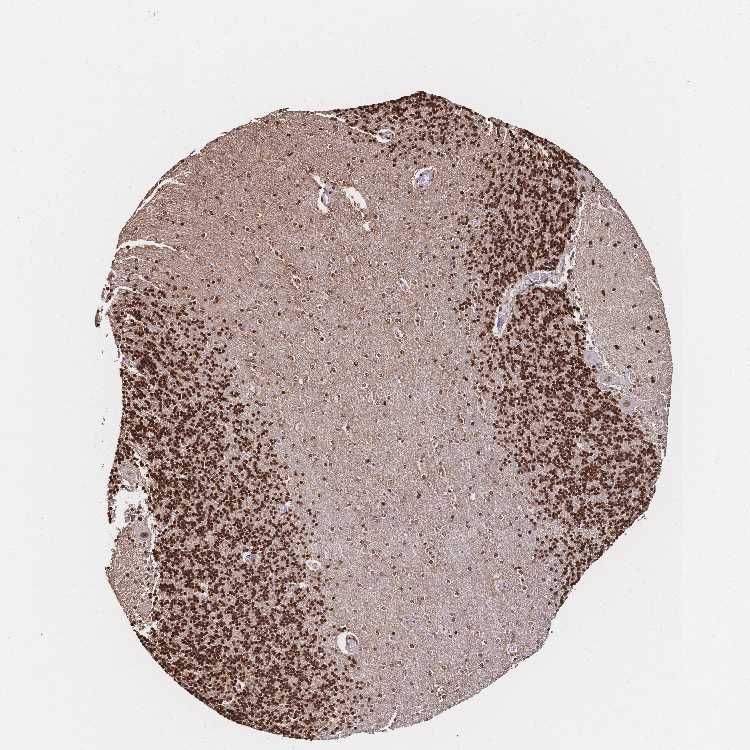

CEREBELLUM - Antibody stainingi

Antibody staining in the annotated cell types in the current human tissue is reported as not detected, low, medium, or high, based on conventional immunohistochemistry profiling in selected tissues. This score is based on the combination of the staining intensity and fraction of stained cells.

Each image is clickable and will lead to virtual microscopy that enables deeper exploration of all samples and also displays staining intensity scores, fraction scores and subcellular localization as well as patient and tissue information for each sample.

Antibody HPA048728Antibody HPA053422Antibody CAB026035

Purkinje cells LowMediumMedium

Cells in granular layer HighHighHigh

Cells in molecular layer HighMediumHigh